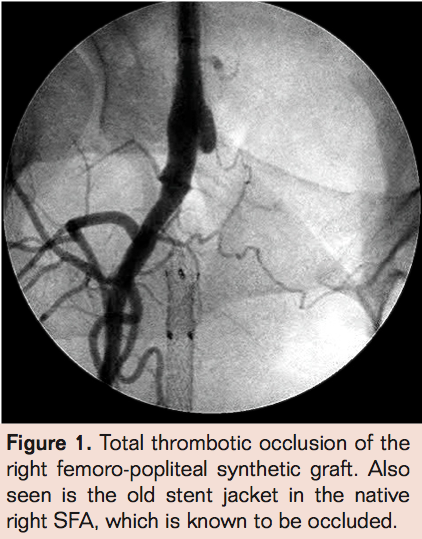

- Laser thrombectomy at 1 mm/sec. with the 2.3 mm probe (Figures 4-9)

Findings

Complete angiographic resolution of thrombus and definitive therapy was achieved in 51 of 78 patients (65.3%) during the index angiographic procedure in the angiographic suite. In 12 of 78 patients (15.3%) flow was established in the index procedure but there was residual thrombus necessitating continued lytic infusion. Of those 12 who had residual thrombus, 11 had complete resolution of thrombus following 3 hours of lytic therapy allowing definitive therapy in the same day. No flow was established during the index procedure for 15 of 78 patients (19.2%). Of these patients angiography via the side hole perfusion catheter showed substantial resolution of thrombus but enough residual thrombus to obstruct antegrade flow in 14 of 15. There was no evidence of thrombus resolution in 1 of 15 patients for whom no flow was established in the index procedure. Of those 15 patients,3 (20%) had complete resolution of thrombus at 3 hours post angiography while 12 of 15 patients (80%) required prolonged lytic infusion. Graft patency was established in 78 of 78 patients but bleeding complications were much less common in the group with successful index procedure than those requiring overnight infusion (2% vs 47% with major bleeding necessitating transfusion of 2 units of PRBC’s in 2 patients who had overnight lytics).